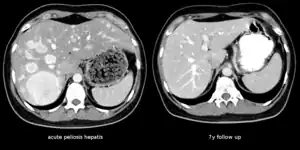

| The CT scan of a patient with peliosis hepatis (left): The follow-up CT (right) after 7 years shows full remission. | |